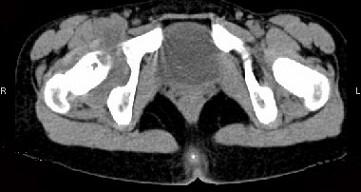

问题 女,11岁,肺部有结核病史,2个月前右髋关节有外伤史,右髋关节部逐渐肿胀疼痛,休息后可减轻,请结合所提供图像,选择最佳选项 ( )

选项 A、右髋关节类风湿关节炎 B、右髋关节痛风 C、化脓性骨关节炎 D、右髋关节退行性变 E、右髋关节结核

答案 E